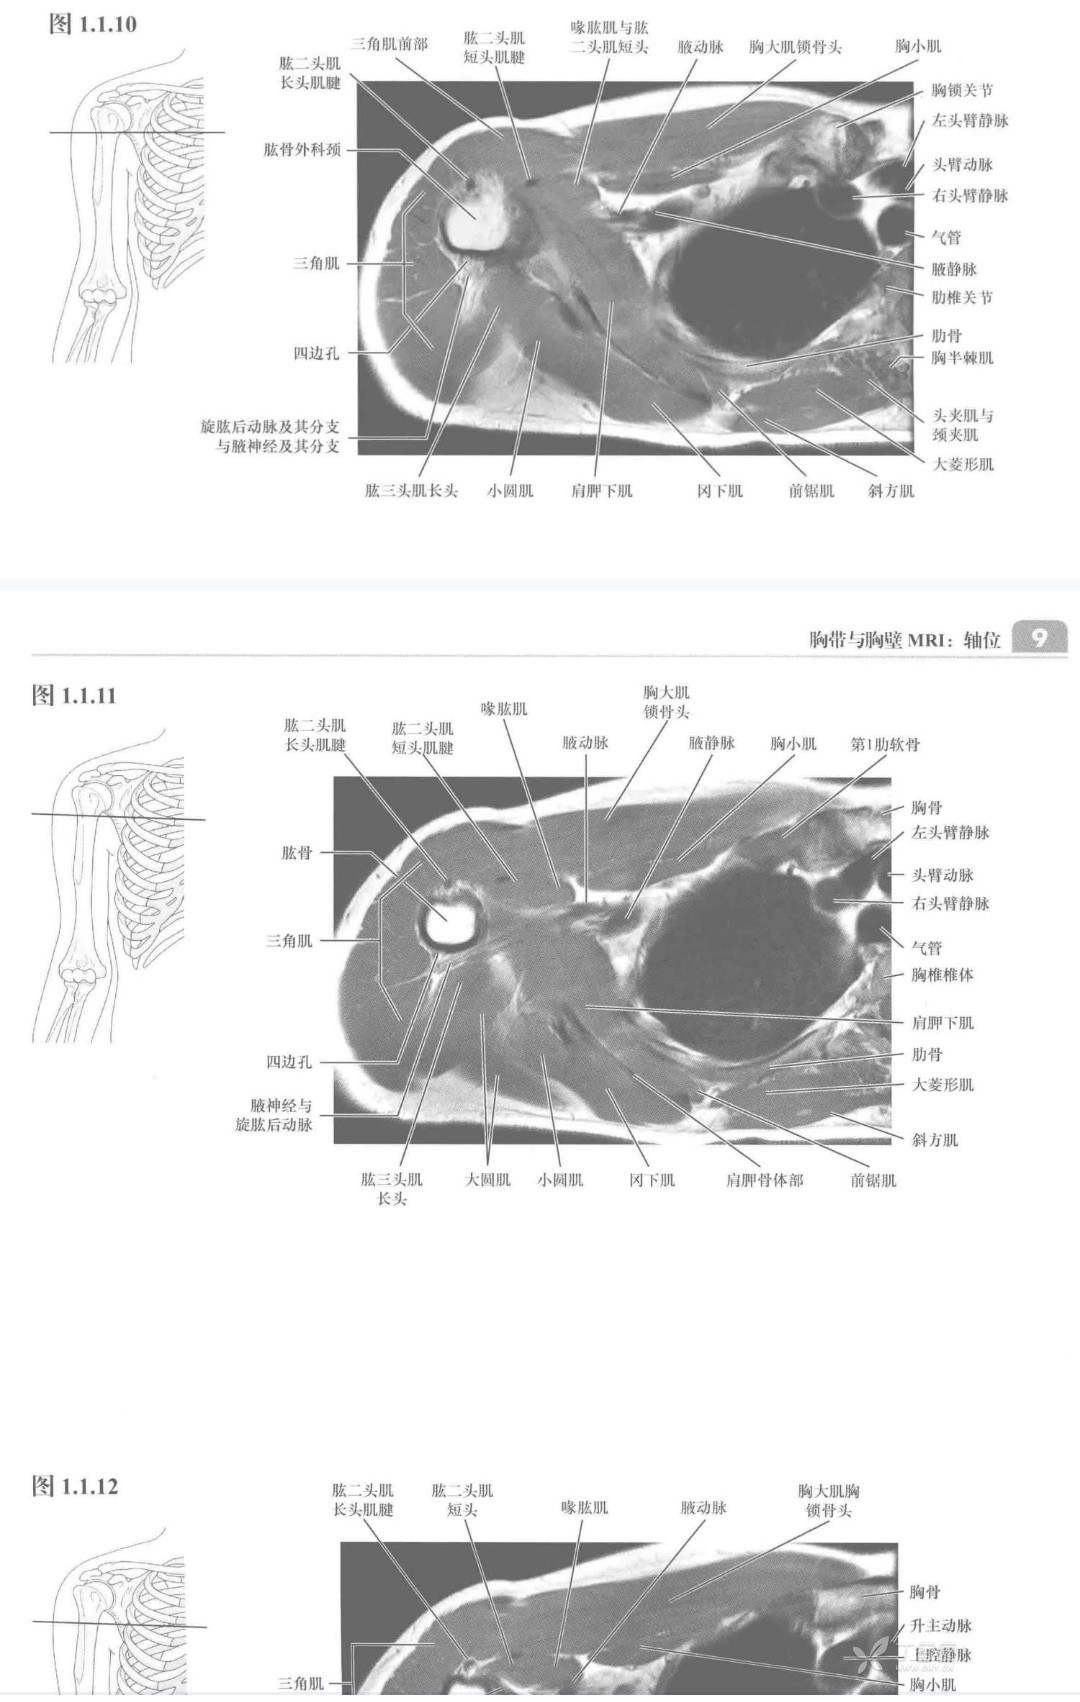

该书的最大特点就是从医学断层影像上明悉人体之解剖结构,全书以身体部位为主线,从横断层面、矢状层面和冠状层面全方位呈现了人体的影像断面解剖结构,并在每一张CT或MRl图像中配上详实的标注,以利于教师的带教和学生的学习,更为医学工作者的专业结构查寻带来便利。骨骼、肌肉与实质脏器的影像解剖是本书中重点介绍的内容,中枢、头颈部、肺与胃肠等空腔脏器影像不是本书重点。本书采用统一格式,连续断层配合肌肉起止点的表格说明,更加方便读者的学习与记忆。除医学影像专业外,临床的骨科、运动医学科、普外科、整形外科、基础解剖教研室等也都适合选择本书作为医疗与教学的参考用书。